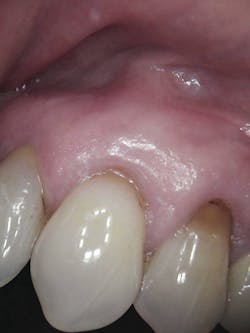

The patient, a 63-year-old female, presented for an emergency visit. She explained her situation, complaining of pain and a lump on the top-left quadrant of her mouth. After an oral evaluation and x-ray (figure 1), it was discovered that she had a large draining granuloma with swelling in the mucobuccal fold near teeth Nos. 12–14 due to a chronic periapical abscess (figure 2).